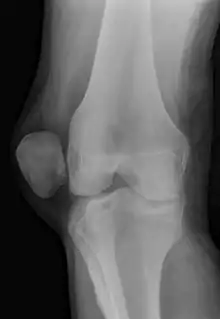

A patellar dislocation is a knee injury in which the patella (kneecap) slips out of its normal position.[5] Often the knee is partly bent, painful and swollen.[1][2] The patella is also often felt and seen out of place.[1] Complications may include a patella fracture or arthritis.[3]

| X-ray showing a patellar dislocation, with the patella out to the side. | |

A patellar dislocation typically occurs when the knee is straight and the lower leg is bent outwards when twisting.[1][2] Occasionally, it occurs when the knee is bent and the patella is struck directly.[1] Commonly associated sports include soccer, gymnastics, and ice hockey.[2] Dislocations nearly always occur away from the midline.[2] Diagnosis is typically based on symptoms and supported by X-rays.[2]